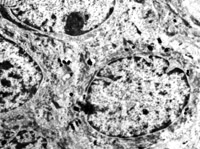

5-2-5 傷后第5天,膠原纖維相互融合,其間的細(xì)胞已崩解  TEM×6000